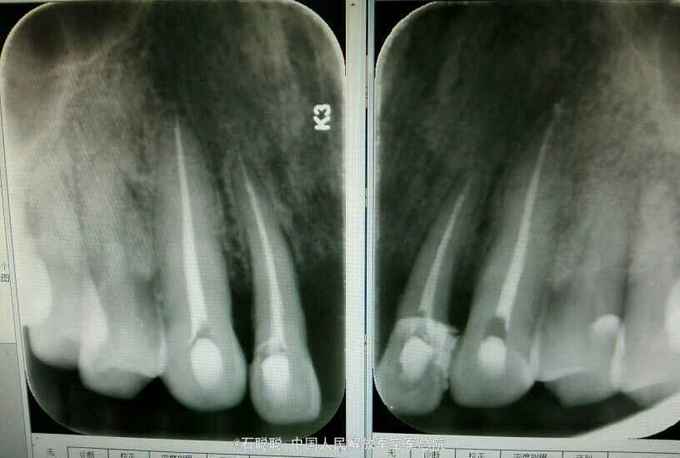

诊断:11、21缺失 治疗计划:向患者交代种植、活动、固定义齿修复方案的优缺点,患者考虑到种植周期长、活动修复难以满足美观要求,选择全瓷固定桥修复方案,但患者12、22基牙条件不甚理想,交代患者修复后要严密观察,定期复诊。 处置:12、13、22、23碧蓝局麻下开髓,拔髓,冲洗,置失活剂,氧化锌暂封 一周后复诊:去除暂封,测量根长,12=22=19mm,扩大至25#,13=23=24mm,扩大至35#,大量冲洗,干燥根管,置CP棉球,氧化锌暂封。 一周复诊:12、13、22、23去除暂封,试主尖,冲洗,干燥,冷测压充填,拍摄根尖片,恰填,置干棉球,氧化锌暂封 一周后复诊:12、13、22、23无不适,去除暂封,磷酸锌垫底,树脂充填,预备牙体,排龈,聚醚取模制作临时冠,调磨粘固 一周后复诊:试戴内冠,就位顺利,边缘密合 一周复诊:试戴全瓷桥,由于边缘密合,固位良好,调节正中咬合、前伸咬合、侧方咬合为轻接触,磨光U200粘固

讨论:在这个病历中,由于12、22牙槽骨有所吸收,并且缺牙区牙槽骨有一定量的丧失,这种修复方式并不推荐,但患者了解各种修复方式优缺点之后,强烈反对种植和活动修复,只能进行固定桥修复,治疗结束后除外嘱咐患者常规义齿戴总注意事项,一定要定期复查,观察基牙情况,防止牙槽骨进一步吸收。在制作义齿时,加工厂为补充缺牙区的牙槽骨吸收,龈端唇舌侧均补充了较多的瓷,可能会使得义齿视觉上比较大,这也是一种折中的做法。